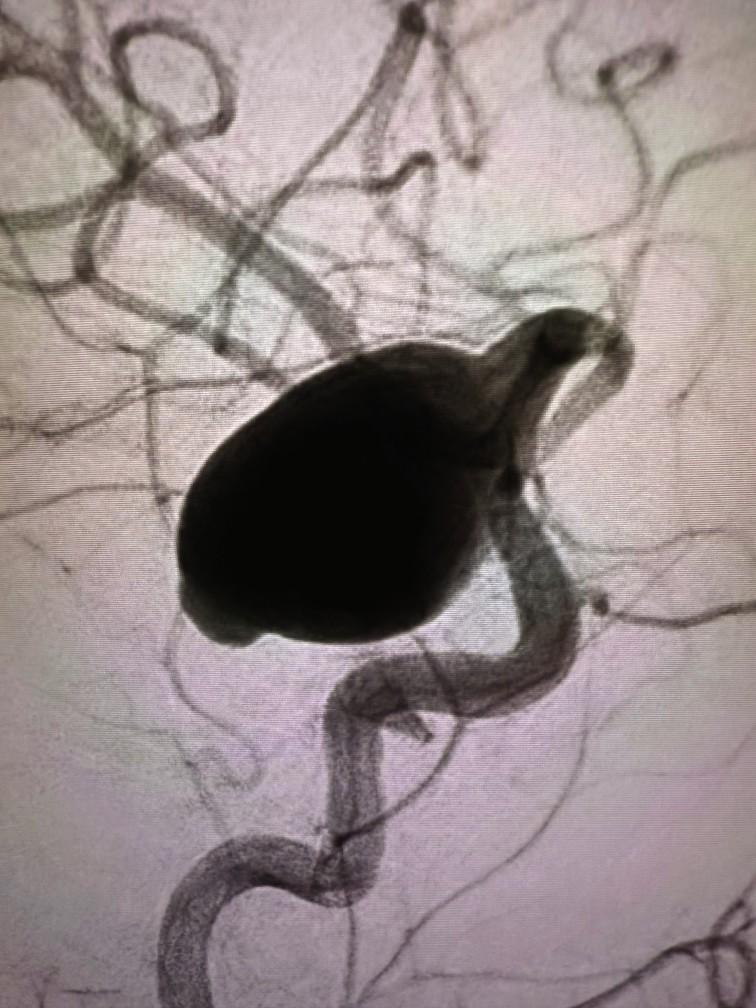

Given her history of migraine headaches, it would have been reasonable to assume Williams’ issues stemmed from that, but the 42-year-old, North Miami resident knew this was a different kind of pain. At her wit’s end, she went to the ER at Memorial Hospital Pembroke where a CT scan revealed a giant brain Aneurysm, the type that when it ruptures kills nearly

50% of its victims. Among the half that manage to survive the brain bleed, nearly 70% are left with cognitive deficits that affect memory, attention, reasoning, problem-solving and decision-making.

“Jada had one of the largest Aneurysms I’ve ever seen,” said Dr. Brijesh P. Mehta, Chief of Adult & Pediatric Neurointerventional Surgery and Medical Director of the Comprehensive Stroke Program at Memorial Healthcare System. “We performed a minimally-invasive endovascular procedure in the cath lab to cut off blood supply to the Aneurysm using a flow diverting device and coils.”

Memorial Neuroscience Institute

Neurointerventionalists care for more than 200 brain aneurysm patients each year, making it one of the largest treatment centers in South Florida. One in every 50 people has the potentially deadly condition, with High Blood Pressure, smoking and family history being the

once again driving, taking care of her children, ages 11 and 14, and contributing to the radio show. But she’s also being cautious to avoid setbacks, with the memories of 10 days of bed rest and six weeks without leaving her home too fresh to forget. What was once, according to Dr. Mehta, “a ticking time bomb,” is now a new lease on life for JadaWilliams. A Brain Aneurysm that could have easily ruptured never did and Williams believes that means she was meant to serve a bigger purpose. “I hope I can be an example to others,” she said. “Your lifestyle matters and you don’t have to be a superwoman.

Listen to your body, advocate for yourself and if you think something isn’t right, get

Memorial Neuroscience Institute: www.mhs.net/services/neuroscience

prehensive treatment, compassionate rological conditions. Few centers can match the depth of its neurological expertise or the wide range of available services.

Part of the Memorial Healthcare System and recognized for its quality and safety, the Comprehensive Stroke Program treats conditions of the Brain that include Acute Strokes, Vascular Malformations, Carotid Stenosis and Arteriovenous Fistulas of the Spine.